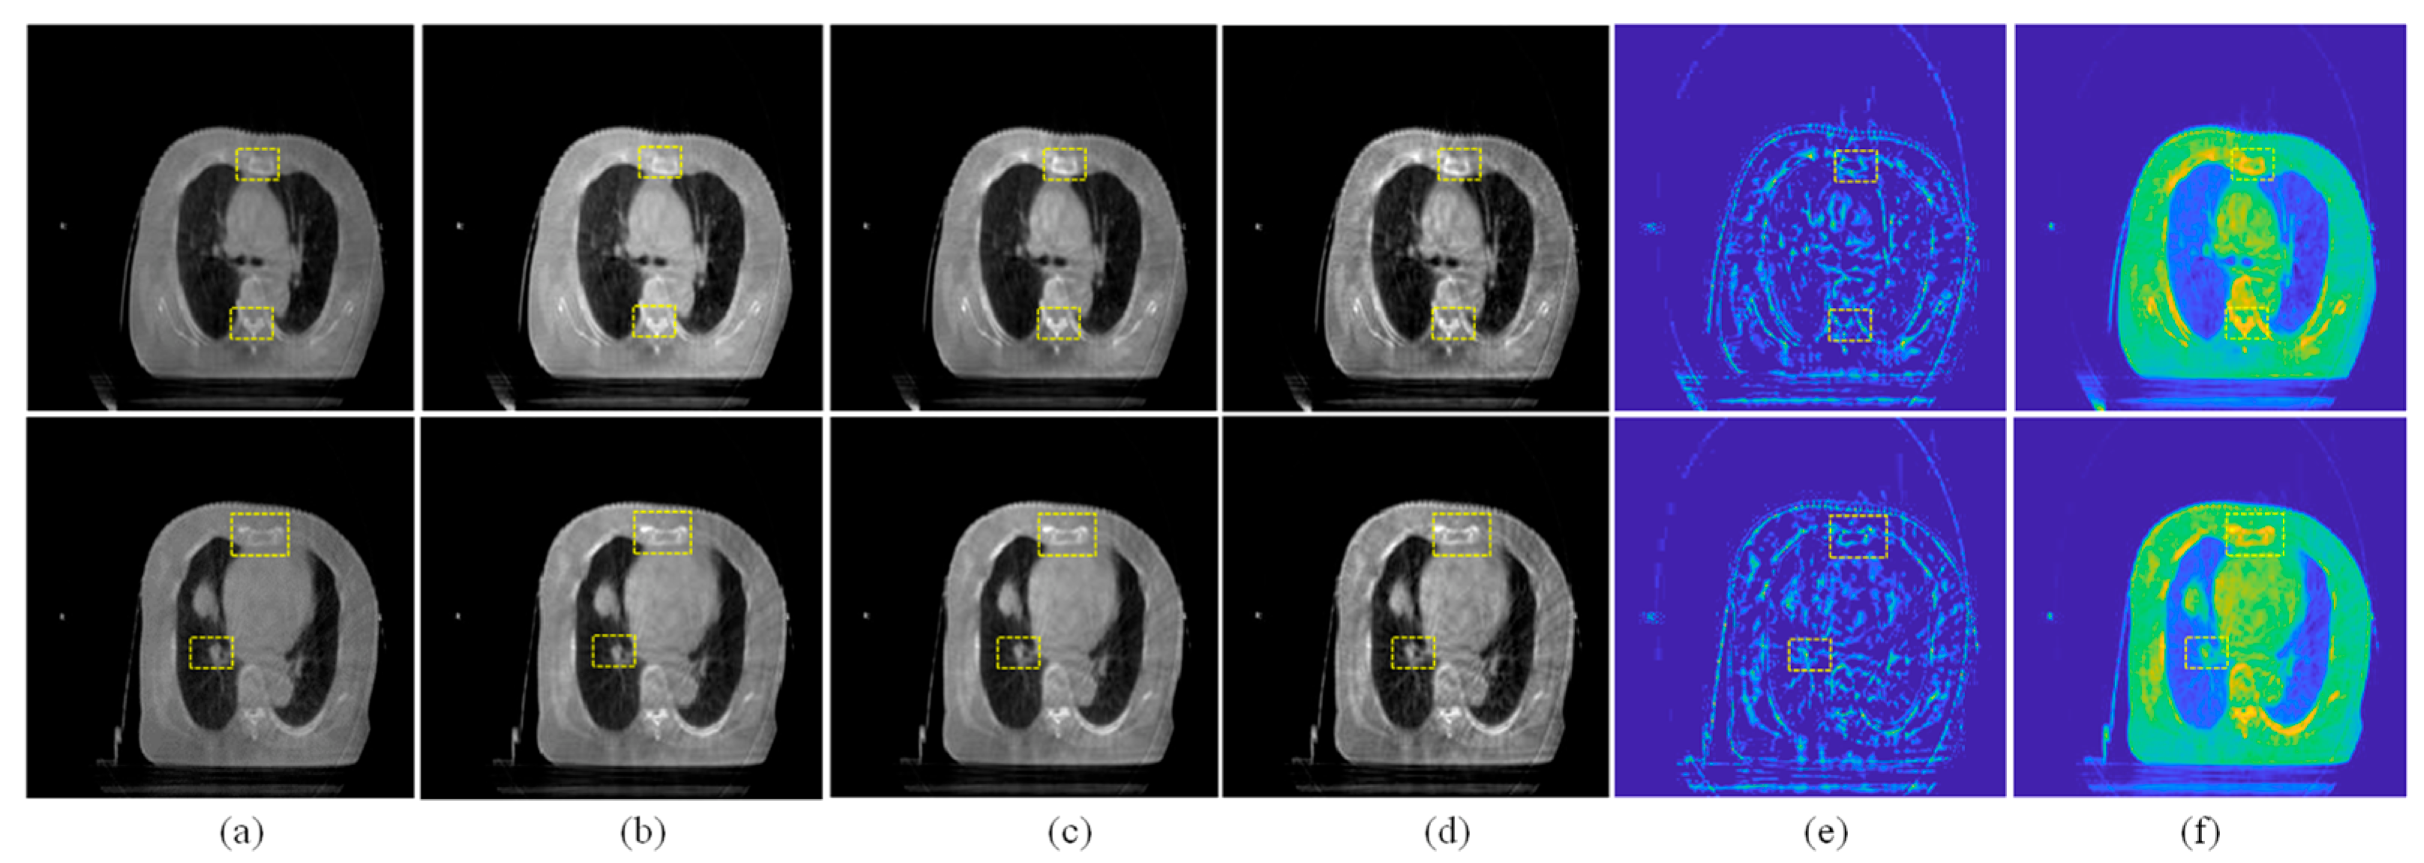

When the visual saliency detection results are obtained by Equation (12), the salient region of the input image will be stretched and enhanced, as shown in Figure 4.

Figure 4.

Examples of visual saliency detection. (a) Source CBCT images. (b) Pseudo-color image of (a). (c) Saliency map of (a). (d) Pseudo-color image of (c).

In the proposed VSFE algorithm, the saliency detection result from Equation (12) will be used as the visual saliency decision map for further detail enhancement. The visual saliency enhancement can be computed by:

where is the enhancing weight parameter, is the reconstructed result by the SSLRA, and is the visual saliency map of .

Some examples of are given in Figure 5c. Compared with the reconstructed results in Figure 5b, the contrast of the visual saliency enhancement images is higher and the important regions are easier to observe.

Figure 5.

Examples of Enhancement. (a) Source CBCT image. (b) of (a). (c) of (a). (d) Final enhanced result of (a). (e) . (f) Difference map between (a,d).